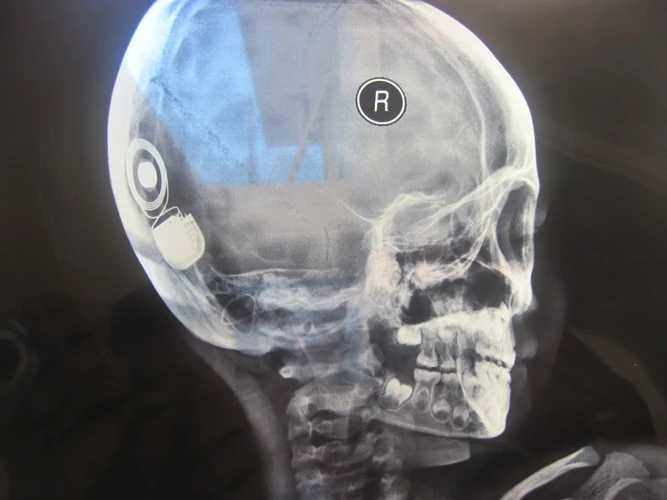

Sau phẫu thuật, qua chụp phim xác định điện cực ốc tai điện tử đã nằm đúng vị trí.